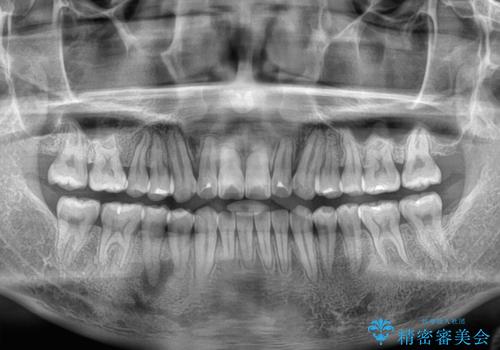

- 八重歯と前歯の隙間を気にして来院された患者様です。

八重歯の改善のため、奥歯を後方に移動させていくこととし、患者様と相談の上、ワイヤー装置にて矯正治療を行うこととしました。

上顎前歯正中の隙間は、舌突出癖によるものと考えられ、舌のトレーニングによる悪習癖改善が必須であるため、徹底するよう指導してから治療を開始することとしました。

舌突出癖が改善されず、なかなか正中の隙間や上下の前歯が接触しなかったために治療が長期化してしまいました。

また、治療期間中のプラークコントロールが悪く、ブラッシング指導も奏功しなかったため、装置の周りが脱灰した状態(初期むし歯)となってしまいました。